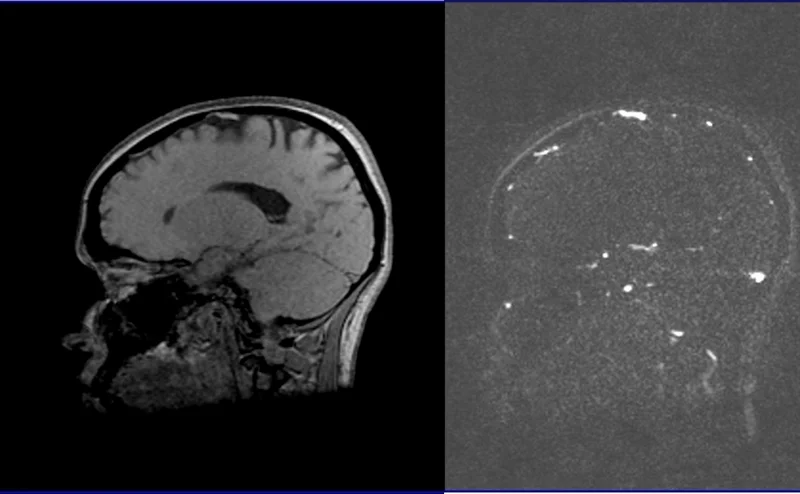

MRV brain phase contrast(PC) 3D images

Post processed MIP images from 3D rowdata